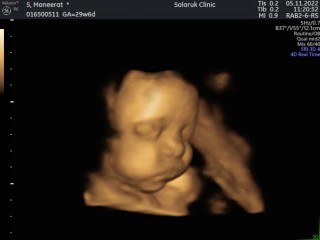

มาอวดรูปลูกชายครับ

คุณพ่อคุณแม่ท่านไหนเห็นหน้าน้องชัดกันแล้วบ้างมาอวดรูปลูกกันครับ